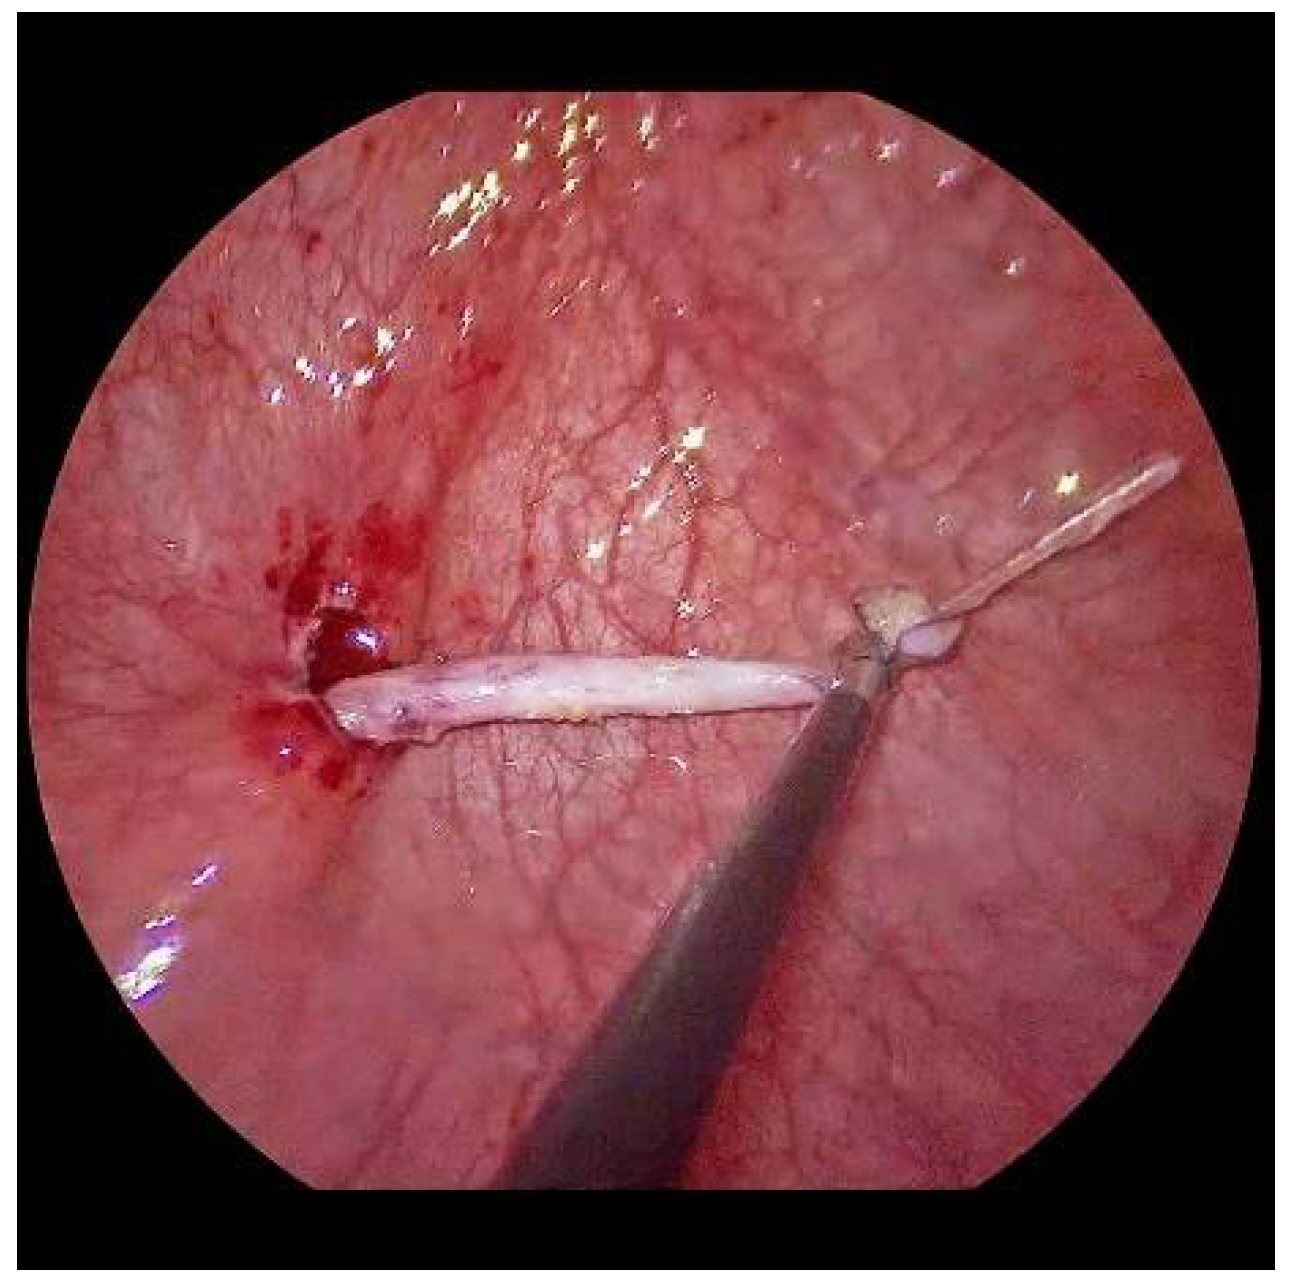

Now, the ureter is intubated with a 3 or 4 Fr. silicone tube, followed by subtle circumferential electrical mucosa incision with a fine dissecting needle (Figure 3). The ureteral release is continued using an electrical hook for at least 4 to 6 cm until it can be positioned without tension to the opposite ostium (Figure 4). Duplicate ureters are intubated twice and mobilized together. If bilateral, the submucosal tunnel is created between the two ostial incisions. If not, an additional mucosal incision is made 1 cm canially of the opposite regular ostium (Figure 5).

Figure 4.

After mobilization, the left ureter can be shifted to the right ostium with little tension.